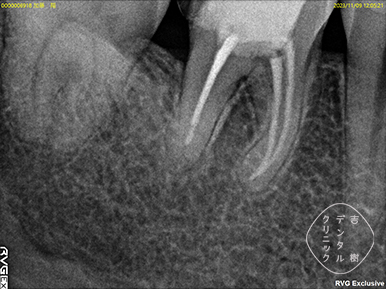

他院で抜歯と診断されたが、当院で根管治療を行い抜歯せずに治療できたケース。

根管治療を行う際には、まず、画像診断を行うことで歯の形状を確認します。通常、多くの歯科医院では「2次元」のレントゲンが使用されますが、この方法では初期の患部を見つけることが難しく、根管の複雑な形状を確実に把握するには不十分です。

そのため、当院では「3次元」の撮影が可能な「CT」を使用しています。CTはお口の周りを360度回転しながら撮影することで、レントゲンでは確認することができなかった細かい部分まで詳細に把握することができます。